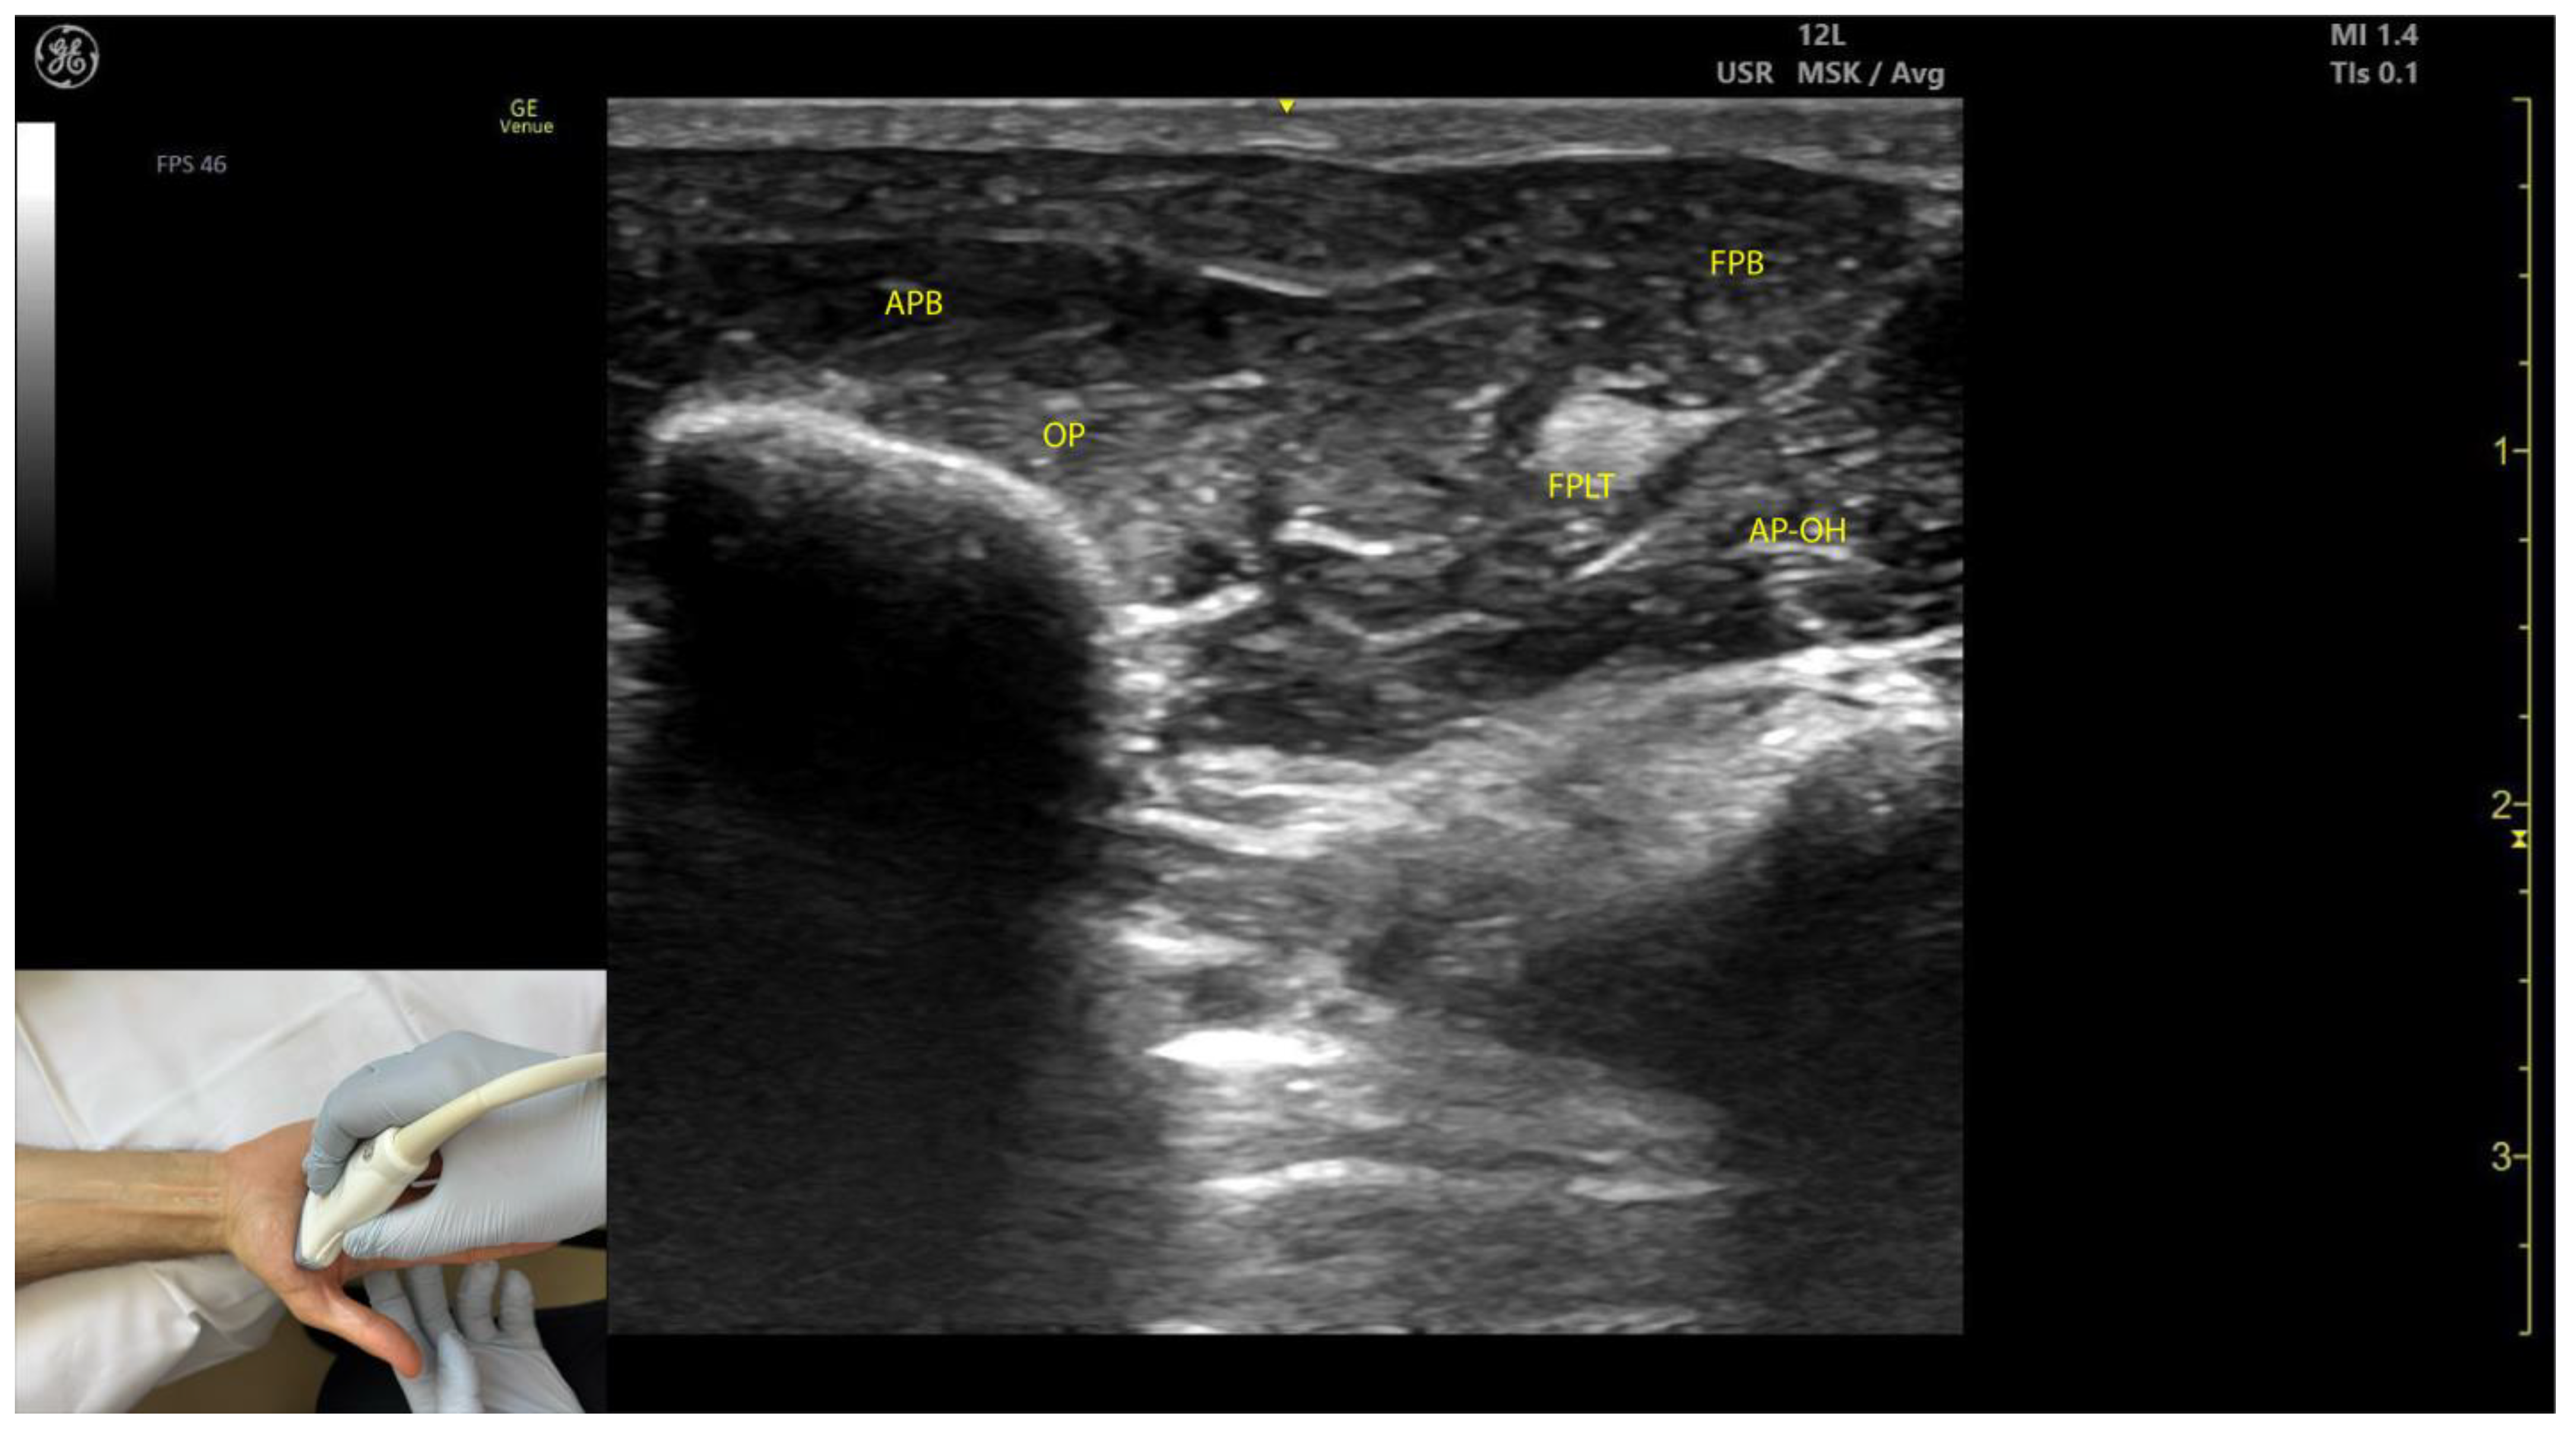

2.8.3. Key Ultrasound Landmarks (Figure 8)

- Muscle position: The APB is the first muscle mass from lateral to medial within the thenar eminence, also being the most superficial muscle mass of the thenar eminence [49].

- External fascia: The APB muscle lacks a pronounced fascia to clearly separate it from adjacent muscle masses, such as the opponens pollicis and flexor pollicis brevis, which can complicate precise localization during BoNT-A injections.

2.8.4. Clinical Implications and Injection Strategy

- The region with the highest density of intramuscular nerve arborizations of the APB is located 40% along the line connecting the hook of hamate to the head of the first metacarpal [51].

- In our clinical practice, the APB is targeted for BoNT-A injections at the point of maximum muscle thickness, determined via ultrasound, typically located at the base of the thenar eminence.

2.9.3. Key Ultrasound Landmarks (Figure 8)

- Muscle position: The OP is the second structure from superficial to deep within the thenar eminence [52].

- Muscle size: It is the largest muscle within the thenar eminence [53].

- Lateral position: The OP is located lateral to the flexor pollicis brevis (FPB) [53].

- External fascia: The OP muscle lacks a pronounced fascia to distinctly separate it from adjacent muscle masses, such as the abductor pollicis brevis and flexor pollicis brevis, which may make precise localization during BoNT-A injections more challenging.

- Dynamic evaluation: Scanning distally toward the MCP joint shows an increase in the size of the OP and a corresponding decrease in the size of the APB. At this level, the tendon of the FPL can be seen deep to the OP [54]. Muscle contraction of the OP is observed during adduction and medial rotation of the thumb at the CMC joint, flexion at the MCP joint, or during thumb opposition when the tip of the thumb contacts the fifth finger [55].

2.9.4. Clinical Implications and Injection Strategy

- The region with the highest density of intramuscular nerve arborizations of the opponens is located 60% along the line connecting the hook of hamate to the head of the first metacarpal [51].

- In our clinical practice, BoNT-A injections into the OP are performed at the point of maximum muscle thickness, as determined by ultrasound. The optimal injection site is typically located approximately 1 cm proximal to the MCP joint on the palmar aspect of the hand. Ultrasound guidance ensures accurate delivery while avoiding adjacent structures, such as the flexor pollicis longus tendon.